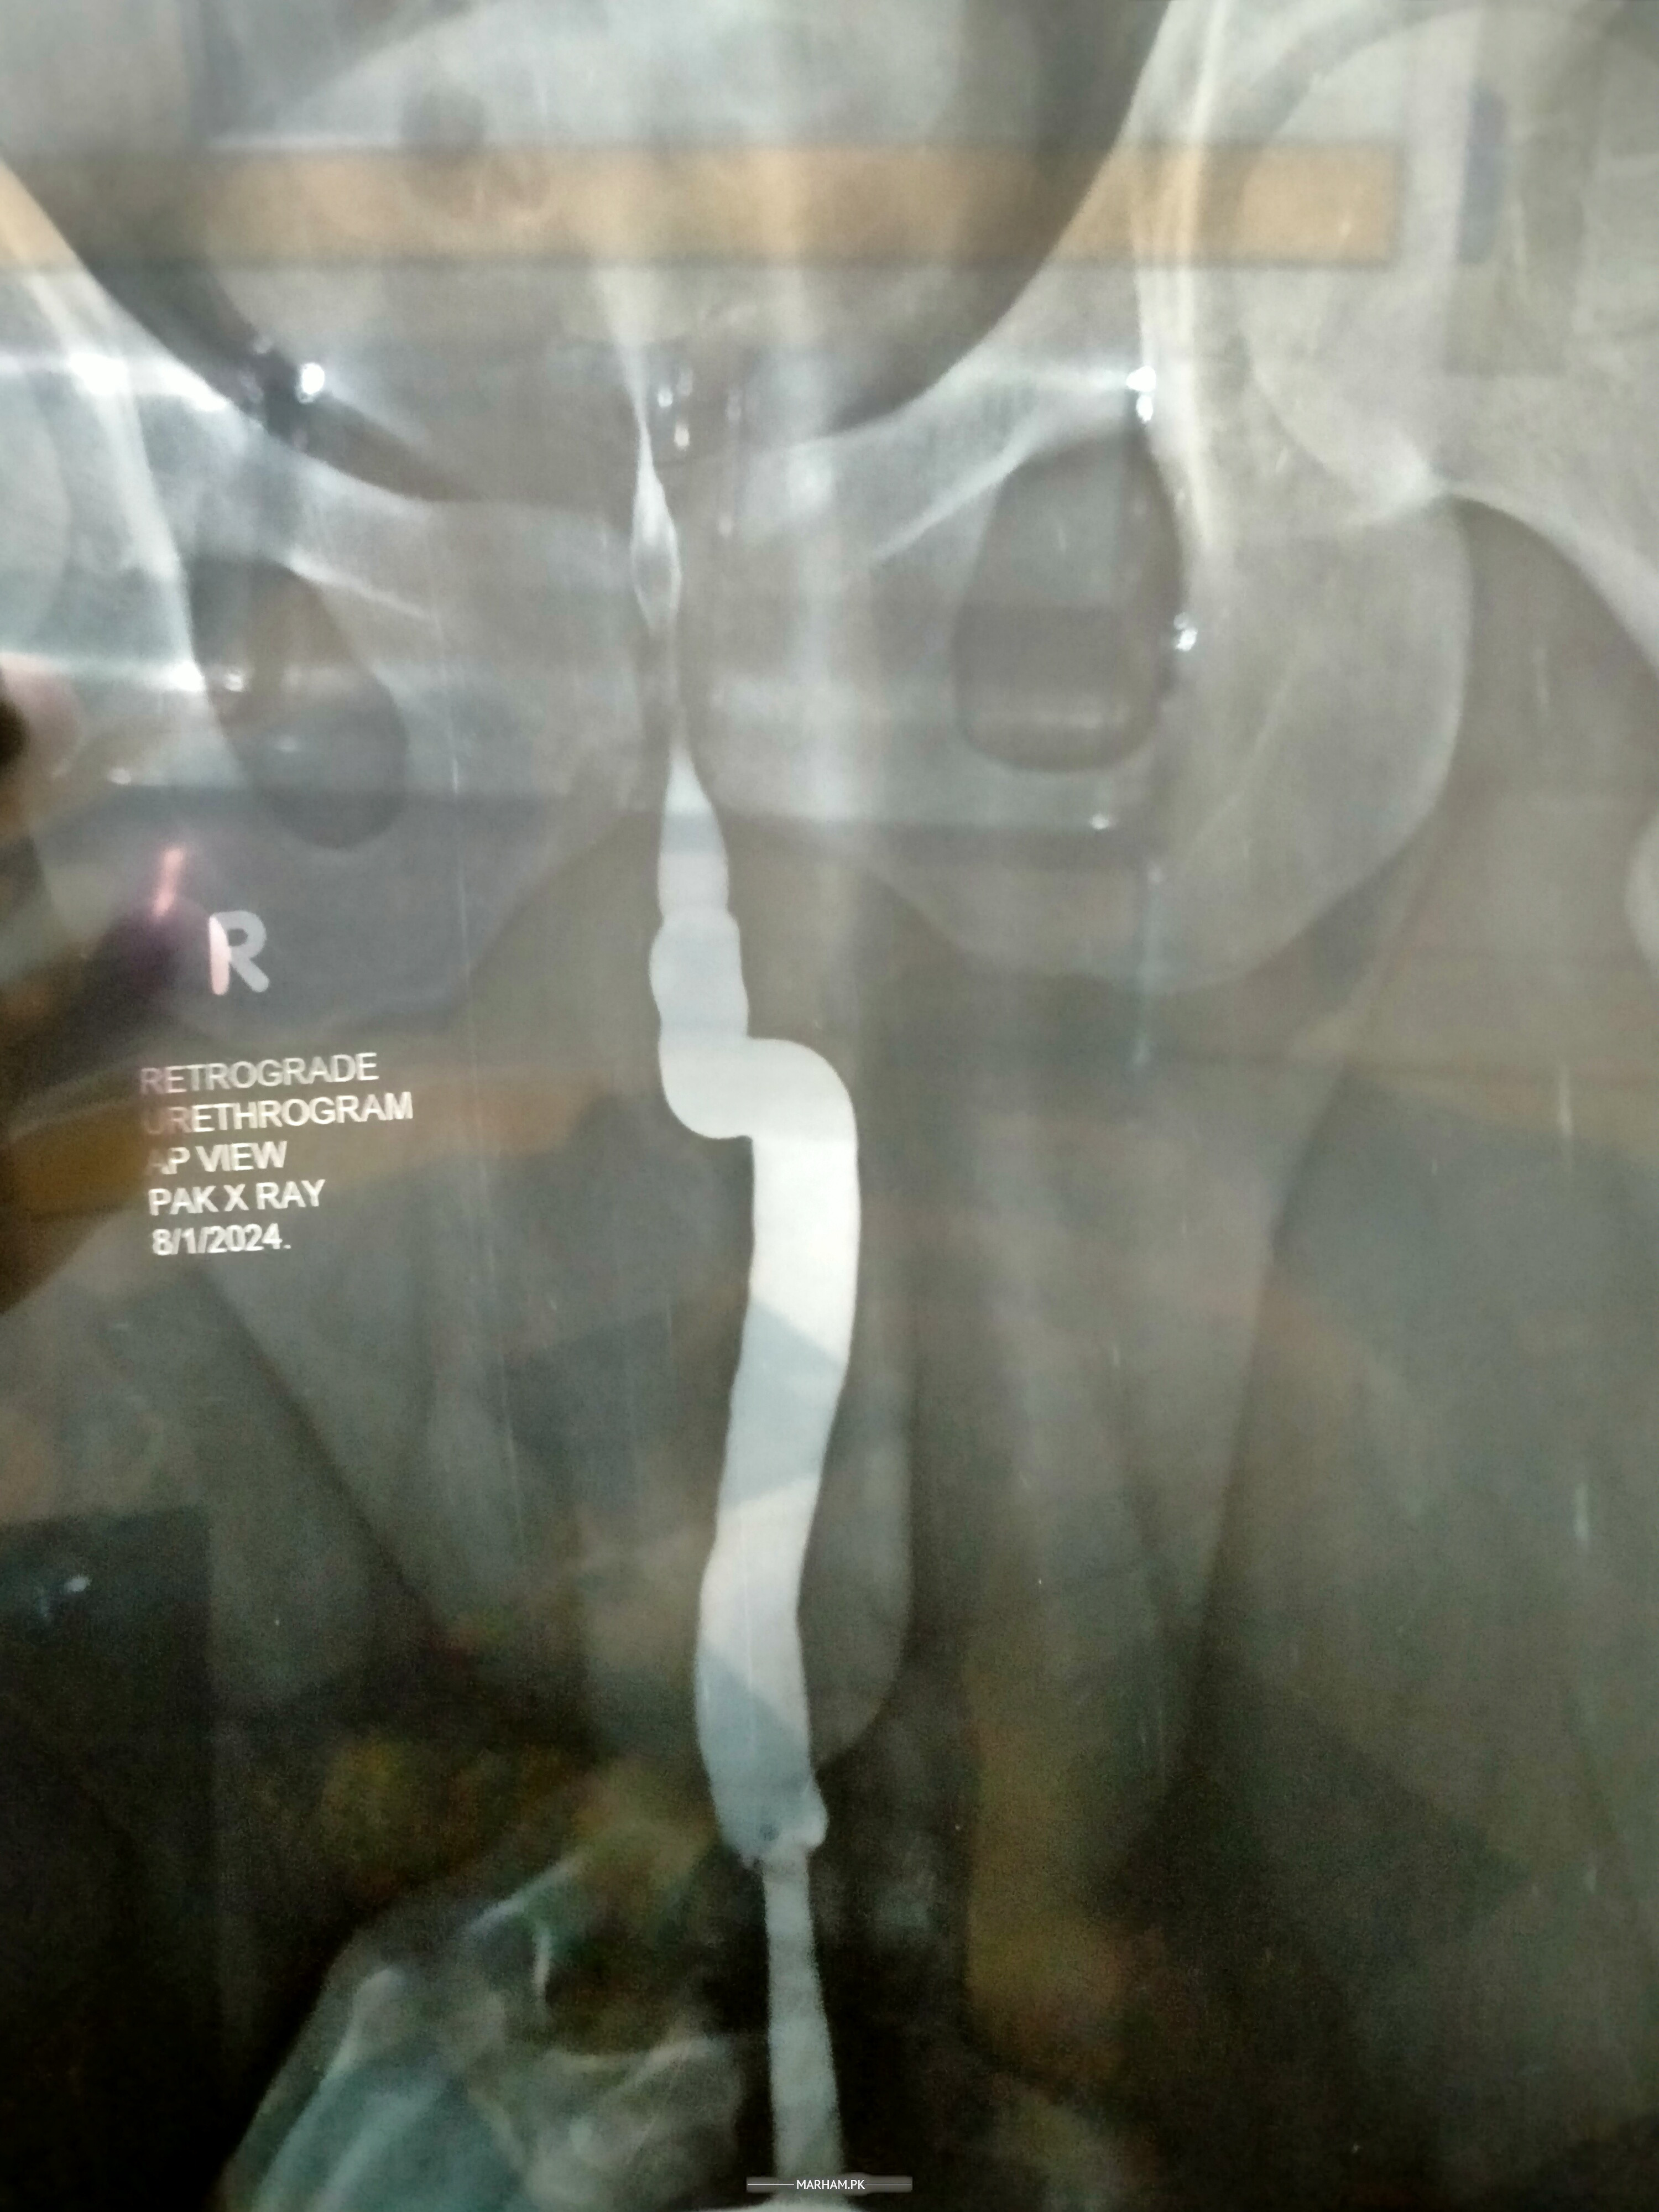

this is my Urethrogram

Poor quality urethrogram. Apparently bulbar stricture.

it shows filling defect at bulbar urethra

Cannot tell from this poor quality urethrogram.